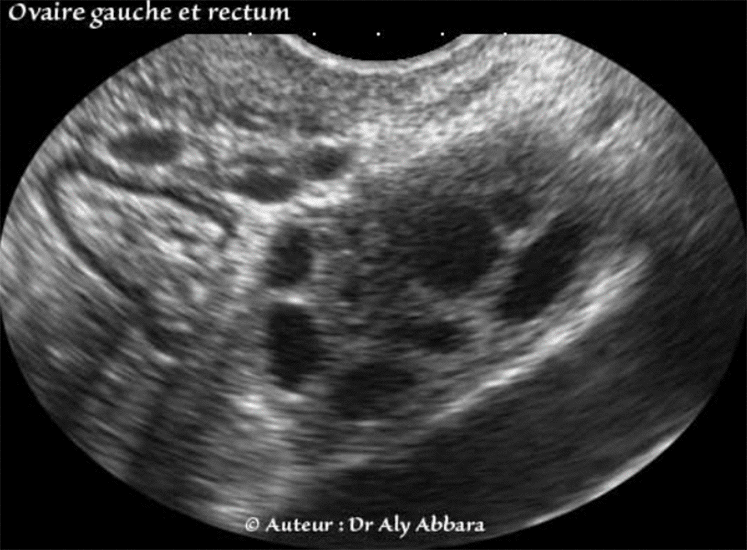

L'ovaire gauche dans sa fosse ovarique (de Krause) gauche, juxtaposant le rectum

On remarque la présence des vaisseaux iliaques internes gauches (seulement la veine est visible sur l'image)

qui forment la limite postérieure de la fosse ovarique chez la femme nulligeste.

Le bord interne de l'ovaire juxtapose le rectum

Anatomie échographique - Ovaire gauche au voisinage du rectum